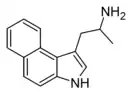

Compound 5 [25] | 1-(3H-benzo[e]indol-1-yl)propan-2-amine | |

|